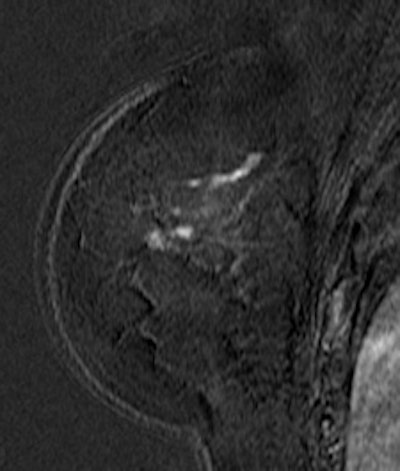

![]() |

| Contrast-enhanced breast MRI (subtracted image three minutes after contrast medium injection). Patient with a diagnosis of invasive ductal carcinoma (ultrasound-guided biopsies). At surgery, no cancer was found. Ultrasound examination after surgery was unable to detect the lesion. At MRI, the lesion was well depicted (inner quadrants, deep location). Image courtesy of Dr. Anne Tardivon. |